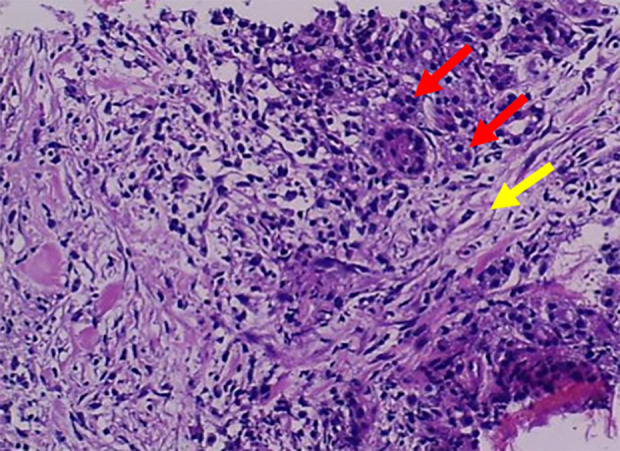

免疫疗法近年来呈指数增长,其相关副作用的研究也呈指数增长。尽管对免疫治疗的广泛反应已被描述,但免疫介导的局灶性胰腺炎的报道仍然很少。与免疫检查点抑制剂相关的自身免疫性胰腺炎发生的原因是T淋巴细胞的过度活化,T淋巴细胞对胰腺细胞起作用,引起炎症。病例报告:本病例报告描述了一位先前健康的41岁男性,诊断为转移性黑色素瘤伴腹股沟淋巴结转移。患者接受了1年的纳武单抗辅助治疗,并具有良好的耐受性。该治疗暂停1年后,淋巴结和腹膜复发发生,导致开始伊匹单抗和纳武单抗联合治疗,随后维持纳武单抗,导致完全缓解。经过10个疗程的纳武单抗治疗后,PET-CT和MRI发现胰腺头部病变,怀疑为原发性肿瘤。患者无症状,肿瘤标志物正常,淀粉酶和脂肪酶水平升高。内镜下超声引导活检排除原发性胰腺癌,发现与免疫治疗相关的中度活动性慢性炎症。尼武单抗治疗中断2周,期间胰酶水平改善。此后恢复治疗。患者继续每月应用纳武单抗,保持完全缓解。成像或实验室检查结果无变化。结论:由于缺乏皮质类固醇干预,炎症的自限性,尽管继续使用免疫治疗,但缺乏炎症复发,该病例是非典型的自身免疫性胰腺炎。

BACKGROUND Immunotherapy has seen an exponential increase recently, as has the study of its associated adverse effects. Although a wide range of reactions to immunotherapy has been described, reports of immune-mediated focal pancreatitis remain rare. Autoimmune pancreatitis related to immune checkpoint inhibitors occurs because of the hyperactivation of T lymphocytes, which act against pancreatic cells, causing inflammation. CASE REPORT This case report describes a previously healthy 41-year-old man with a diagnosis of metastatic melanoma with inguinal lymph node metastasis. The patient underwent 1 year of adjuvant treatment with nivolumab and had excellent tolerance. After a 1-year suspension of this treatment, nodal and peritoneal recurrence occurred, leading to the initiation of combined therapy with ipilimumab and nivolumab, followed by maintenance nivolumab, resulting in a complete response. After 10 cycles of nivolumab, PET-CT and MRI identified a lesion in the head of the pancreas, which was suspected to be a primary neoplasm. The patient was asymptomatic, with normal tumor markers and elevated amylase and lipase levels. An endoscopic ultrasound-guided biopsy was performed to rule out primary pancreatic cancer, revealing moderately active chronic inflammation associated with immunotherapy. Nivolumab treatment was interrupted for 2 weeks, during which pancreatic enzyme levels improved. Treatment was resumed thereafter. The patient continued with monthly nivolumab applications, maintaining a complete response. without changes in imaging or laboratory test results. CONCLUSIONS This case is atypical for autoimmune pancreatitis owing to the absence of corticosteroid intervention, self-limiting nature of inflammation, and lack of inflammatory recurrence despite the continued use of immunotherapy.